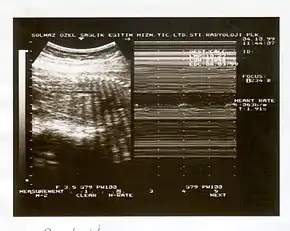

A biophysical profile (BPP) is a prenatal ultrasound evaluation of fetal well-being involving a scoring system,[1] with the score being termed Manning's score.[2] It is often done when a non-stress test (NST) is non reactive, or for other obstetrical indications.

The BPP has 5 components: 4 ultrasound (US) assessments and an NST. The NST evaluates fetal heart rate and response to fetal movement. The five discrete biophysical variables: